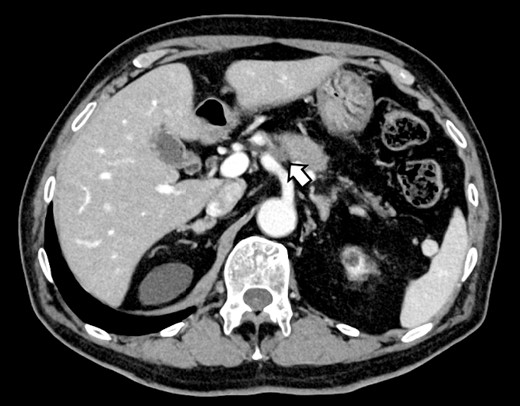

(A, B) CT on postoperative day 48. Contrast-enhanced CT showing a pseudoaneurysm at junction of the GDA and PHA (arrow).

Subsequently, interventional radiology (IVR) was performed. However, because the inferior pancreaticoduodenal artery (IPDA) was very narrow, the microcatheter could not be followed, and hemostasis with IVR was difficult. Therefore, on POD 48, relaparotomy pseudoaneurysm repair was performed. The abdomen was opened through an inverted L-shaped incision, and adhesiolysis was performed, after which a pseudoaneurysm was revealed at the junction of the GDA and PHA. Four transfixing sutures with 3–0 prolene were used. After confirming that the liver blood flow was maintained, surgery was completed. However, bloody drainage from the drain was observed on POD 56. CeCT revealed a pseudoaneurysm (Fig. 3A and B). IVR was considered difficult because of the narrow blood vessels; therefore, the patient underwent a second laparotomy for hemostasis. A pseudoaneurysm was further observed at the junction between the GDA and PHA. In this operation, we used deeper and wider penetrating sutures than in the previous surgery to completely halt blood flow in the GDA. We confirmed that the blood flow to the liver was maintained; however, it was deemed weak. The patient had an uneventful postoperative course without bleeding, and CeCT performed on POD 61 confirmed the disappearance of the pseudoaneurysm. Although the blood flow in the PHA could not be confirmed, the right and left hepatic arteries were preserved (Fig. 4). On POD 76, CT revealed no liver abscesses or infarctions. The drain was removed on POD 78, and the patient was finally discharged on POD 107 without rebleeding or liver failure.